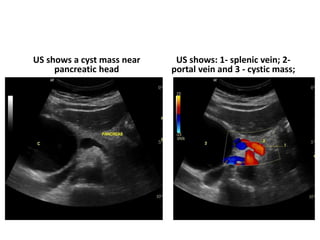

US shows a cyst mass near

pancreatic head

US shows: 1- splenic vein; 2-

portal vein and 3 - cystic mass;